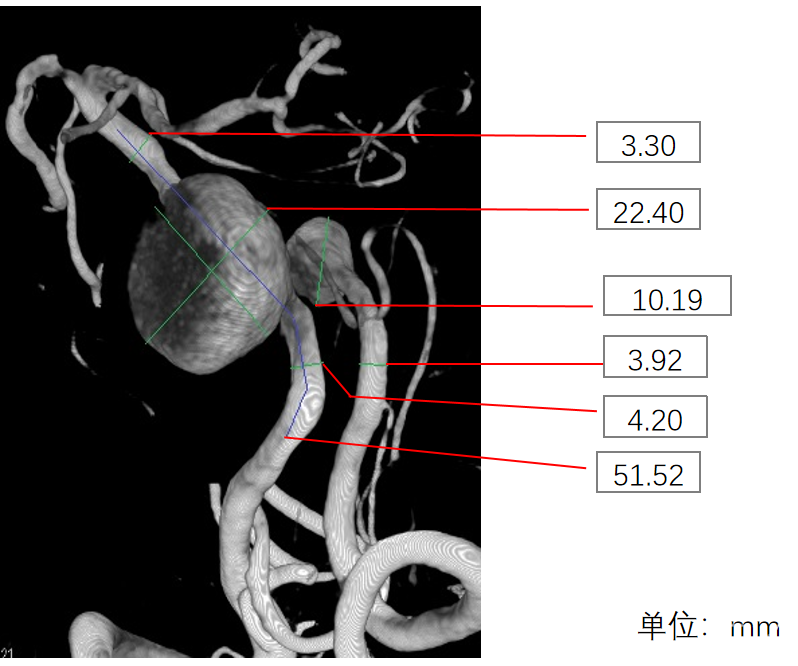

术前影像学资料

右侧椎动脉

左侧椎动脉

1、该患者属于串联动脉瘤,累及左椎动脉V4段末端和基底动脉近端。其中基底动脉近端为富穿支区域,常规介入治疗面临较高的缺血并发症。